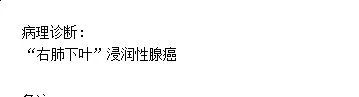

术中快速病理示浸润性腺癌。

常规病理示:浸润性腺癌,腺泡型50%,贴壁型50%,中分化。淋巴结未见转移。